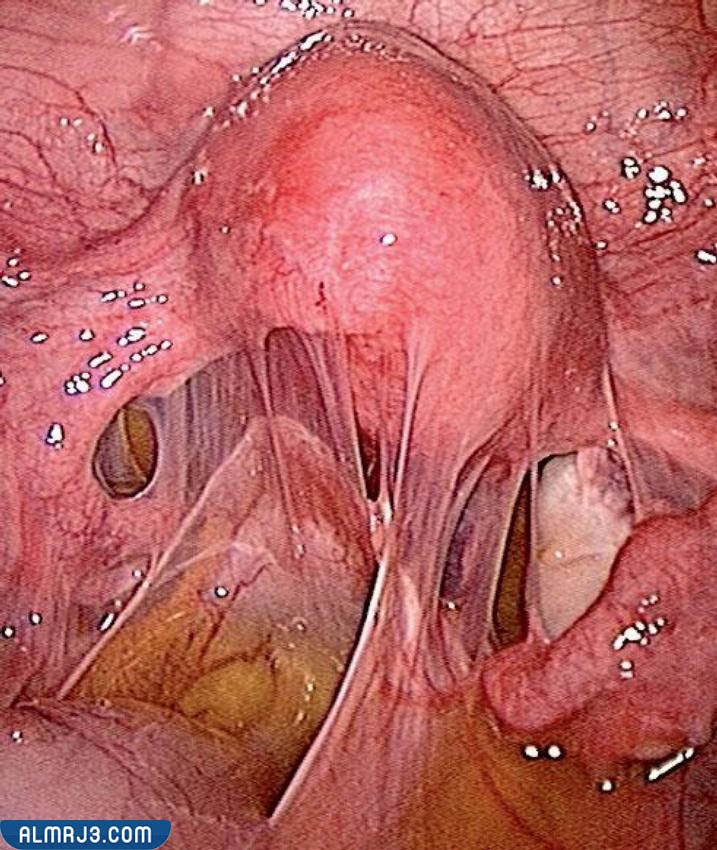

- المنظار: وهي الطريقة الأخيرة التي يتم فيها عمل شق جراحي في بطن المرأة وإدخال كاميرا صغير إلى منطقة الحوض تسمى بالمنظار لتصوير الجسم من الداخل.

علاج بطانة الرحم المهاجرة بالمنظار

يتم علاج هذا المرض جراحيًا بهذه الطريقة كالآتي:

- يتم عمل شق صغير في منطقة البطن.

- يتم إدخال كاميرا صغيرة إلى البطن تسمى المنظار لتصوير الجسم من الداخل.

- يقوم الطبيب بإدخال بعض الأدوات الطبية واستئصال الأنسجة الزائدة اعتمادًا على ما يراه عبر المنظار بدون الحاجة لعمل شق كبير في البطن.